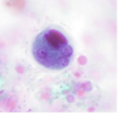

ENTAMOEBA HISTOLYTICA

Professor: Dr. Glena Fe A. Yapchulay-Alcabasa